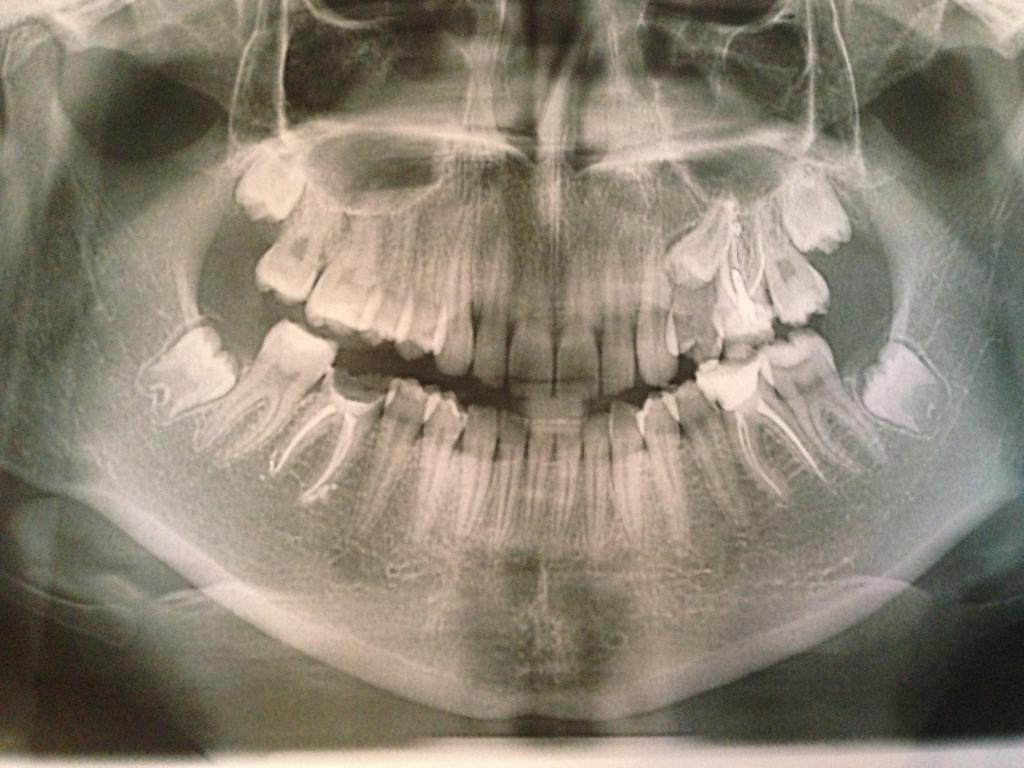

У меня после лечения первого нижнего зуба с левой стороны разболелось полчелюсти. Я полоскала, думала пройдёт, нерв ведь удалён. Но через время пришлось идти к парадонтологу, которая сказала, что там был двухсторонний абсцесс. На десне делали разрез, воспаление прошло, но через 10 дней дней появился новый свищ. Выяснилось, что проблема была в левой нижней двойке, в которой нерв был уже мёртвый. Когда канал двойки запломбировали, свищ почти прошёл. Может можно обойтись без операции? А если всё-таки делать, насколько обширной она должна быть?

На первом снимке сверху слева направо 2,1,1,2,3,4,5. на нижнем в центре 2,1,1. На остальных эти же передние зубы справа и слева.

Мне кажется, что делать прийдется, т.к. по снимку видны изменения костной ткани. т.е процесс достаточно давний, давший уже не первое обострение, и, судя по тому объему материала, который виден на снимке после пломбировки, этому материалу было куда и через что "выходить" - видимо, идет резорбтивный процесс в области верхушки корня... Масштабность и объем вмешательства будет виден только глазами, стоматологу-хирургу, в ходе операции, и должен будет быть балансом межу тем, чтобы иссечь все ненужное и чтобы от зуба что то осталось... как то так....

Если свищ стал исчезать, то можно пока понаблюдать и периодически делать контрольные рентгенограммы. У меня была пациентка, которой мы смогли восстановить костную ткань консервативным методом. Но я ее наблюдала в течение года. Операция не понадобились. Но более точную информацию можно дать при очной консультации. И еще вопрос: на рентгенограмме в апикальной трети достаточно сильно расширен корневой канал? Или это неточности при проведении рентгенограммы?

Стоимость зависит от рас писанного плана лечения. Необходима очная консультация для описания плана лечения и соответственно стоимости. При себе желательно иметь результаты общего анализа крови, анализ крови на сахар и панорамную рентгенограмму